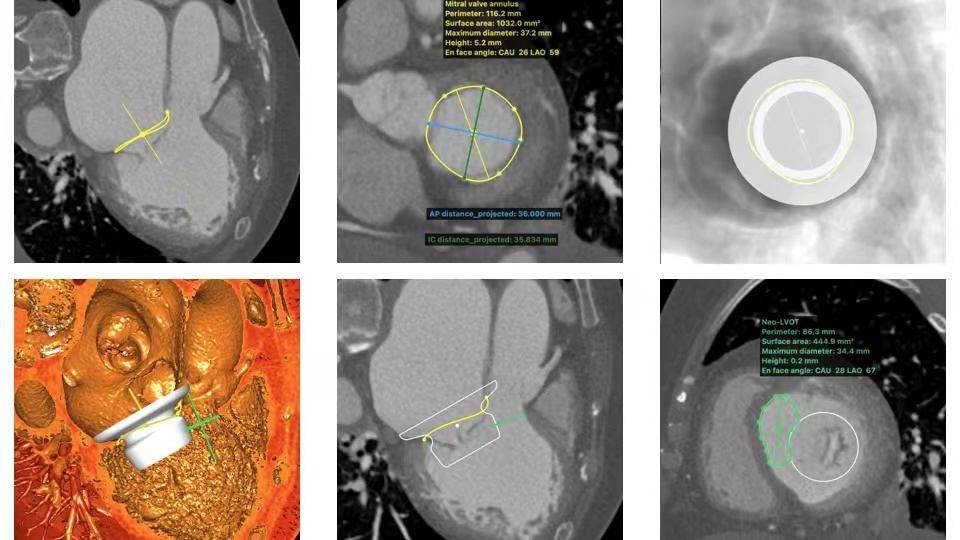

术前,陈茂教授带领团队通过详细的CT测量分析,判断评估患者术中风险并规划手术策略。通过CT影像分割三维二尖瓣瓣环、测量其径线、计算二维投影径线并模拟植入Peijia HighLife TSMVR瓣膜,预判人工瓣膜与毗邻组织贴靠位置良好且无左室流出道梗阻风险。该例患者心室内肌小梁结构复杂,导丝可能易缠绕,因此术中输送器需要准确保持在合适深度,导丝成环过程中需始终维持高位(靠近二尖瓣环底部位置)环绕二尖瓣瓣叶形成通路,以避免植入固定环时位置靠下导致瓣膜释放时移位。

固定环植入

固定环位置评估

瓣膜释放

瓣膜最终形态